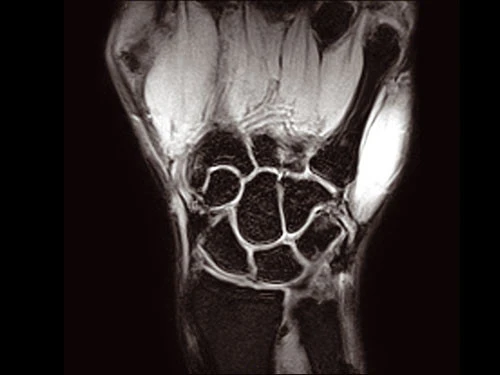

O-scan Впечатляющее качество изображения

Высокопроизводительная система O-scan обеспечивает впечатляющее качество визуализации и экономичное функционирование с низким порогом рентабельности: с системой может работать только один оператор.

Система оснащена очень компактным магнитом с удобным стулом для пациента и охватывает все конечности и суставы: колена, голени, лодыжки, ступни, руки, запястья, предплечья и локти.